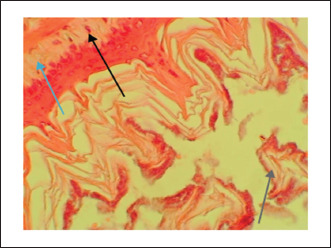

Results: The study found that the extract effectively protected against indomethacin-induced gastric mucosal injuries. It showed a significant (p < 0.05) reduced the severity of lesions and increased the percentage protection of ulcers. The extract also decreased gastric acidity and increased mucus production, indicating its cytoprotective properties. Histopathological examination revealed that the extract prevented morphological changes such as inflammation, necrosis, and ulcers caused by indomethacin. Statistical analysis was performed to determine significant differences between groups.